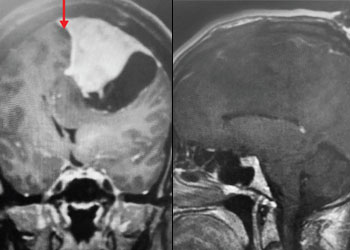

Brain:

Neurosurgeons Collaborate to Treat Giant Symptomatic Meningioma

Author: Ramin Rak M.D., F.A.A.N.S., F.C.N.S., Jonathan L. Brisman M.D., F.A.C.S., Read More!